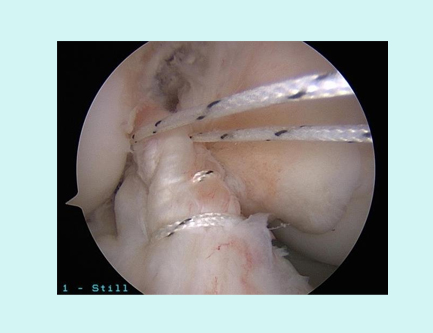

MOST COMMON INJURY IN ELDERLY IS CUFF TEAR WHICH IS AGE RELATED MOST OF THE TIMES. THIS REQUIRES REPAIR FOR NORMAL FUNCTIONING OF SHOULDER.